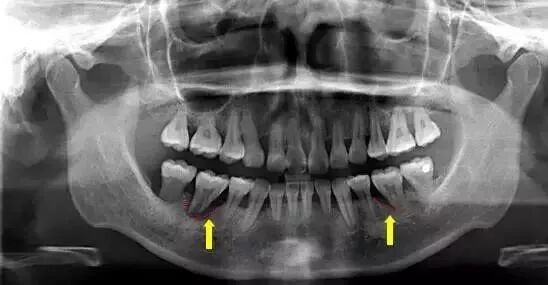

对于第一次来口腔医院检查,或者已经出现严重口腔问题的患者,医生会建议先对口腔做一个X光或者CT扫描检查。

毕竟肉眼只能看到牙齿露出的部分,对那些隐藏在牙龈、牙槽骨里面的情况医生无法精准判别。X光片可以透视出牙齿的内在情况,以便医生对牙齿情况有一个更全面的了解。